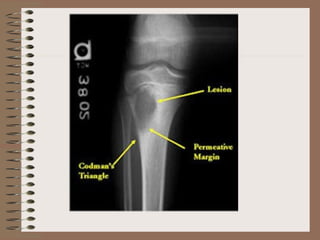

Gross : Osteosarcomas are bulky tumours that

Codman‘s triangle formed by the tumour

lifting the periosteum and forming a triangle

between the periosteum and the bone is seen.

X ray – The tumour elevates the perostium to

form cod man triangle formed by the angle

between the elevated periosteum and the

surface of the involved bone . Sunburst pattern

due to osteogenesis within the tumour may also

occur

of haemorrhage andcystic degeneration. Codman‘s triangle formed by the tumour lifting the periosteum and forming a triangle between the periosteum and the bone is seen. Microscopy : The hallmark of osteosarcoma is the formation of osteoid by malignant mescenchymal cells. This is seen in the form of islands of primitive bony trabeculae ( osteoid) hugged by a rim of malignant osteoblasts. Mesenchymal cells in between osteoid may be spindle shaped , round , oval or polygonal . May be uniform or pleomorphic with bizarre hyperchromatic nuclei and frequent mitotic figures. Sometimes giant cells are present.

X ray –The tumour elevates the perostium to form cod man triangle formed by the angle between the elevated periosteum and the surface of the involved bone . Sunburst pattern due to osteogenesis within the tumour may also occur Parosteal (Juxta cortical ) osteosarcoma arise from the external surface of the bone ( parosteal or juxta cortical means outer to the cortex ) This has better prognosis